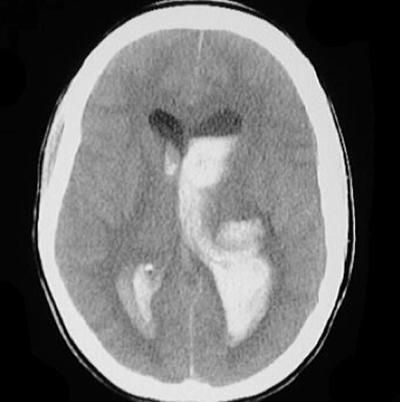

Step 4: Ventricles

Ventricles

Examine for IIIrd, IVth and lateral ventricles for dilation or compression/shift.

Pathologic processes cause dilation (hydrocephalus) or compression/shift. Communicating vs. Non-communicating. Communicating hydrocephalus is first evident in dilation of the temporal horns (normally small, slit-like). The lateral, IIIrd, and IVth ventricles need to be examined for effacement, shift, and blood.